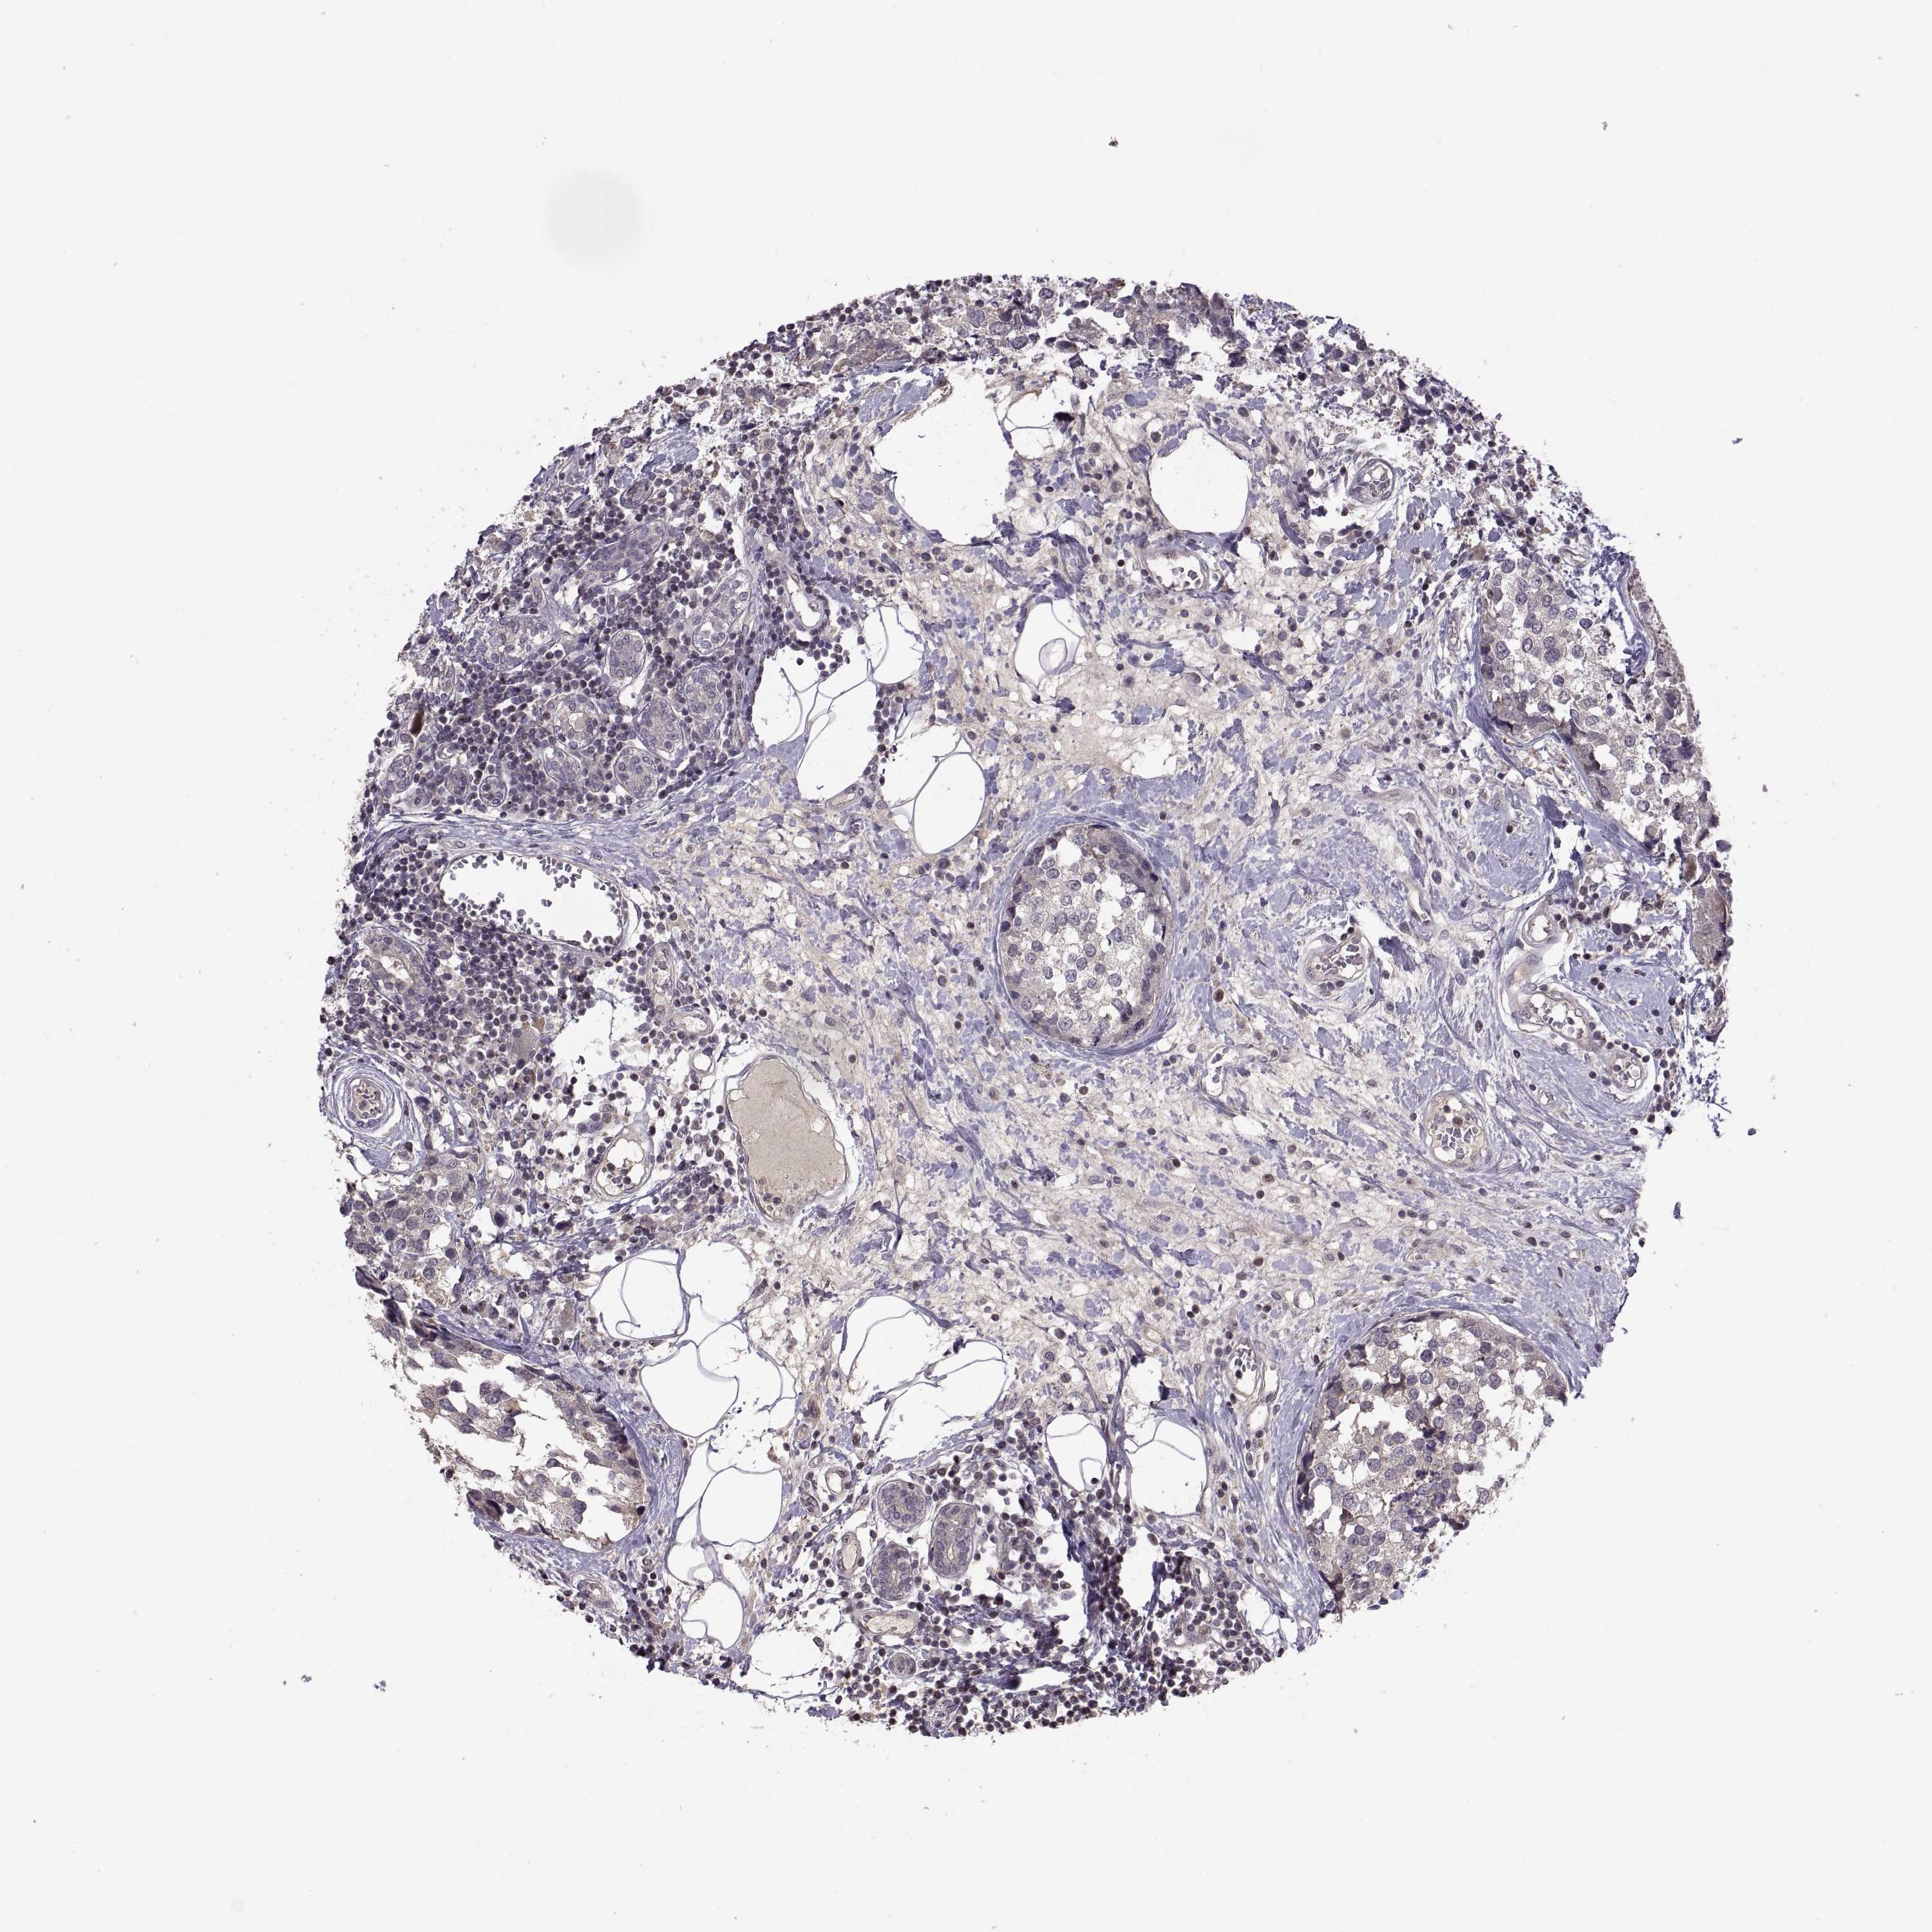

CANCER BREAST CANCER Show tissue menu

BRCA TCGA BRCA VALIDATION PROTEIN EXPRESSION